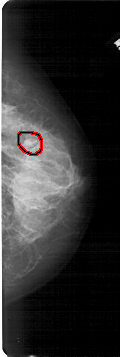

A_1682_1.RIGHT_CC

RIGHT_CC LINES 5341 PIXELS_PER_LINE 1786 BITS_PER_PIXEL 12 RESOLUTION 43.5 OVERLAY

FILE: A_1682_1.RIGHT_CC.OVERLAY

TOTAL_ABNORMALITIES 1

ABNORMALITY 1

LESION_TYPE MASS SHAPE OVAL MARGINS OBSCURED

ASSESSMENT 4

SUBTLETY 3

PATHOLOGY BENIGN

TOTAL_OUTLINES 1

BOUNDARY